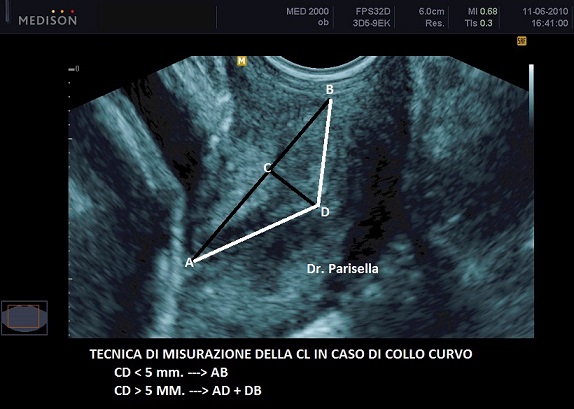

Se il canale cervicale non è diritto ma curvo la misurazione della CL viene effettuata in due fasi: si fa la somma di due linee rette che seguono la curvatura. In questo caso la scelta di effettuare una unica misurazione tra i due orifizi uterini o di ricorrere alla doppia misurazione dipende dal grado di curvatura; la tecnica è la seguente: si traccia una retta che congiunge i due orifizi uterini e si misura l'altezza tra questa retta e l'apice della curvatura; se la distanza è maggiore di 5 mm. si ricorre alla tecnica della doppia misurazione; se la distanza è inferiore a 5 mm. si misura direttamente la distanza tra i due orifizi uterini (vedasi immagini 1-2-3-4).